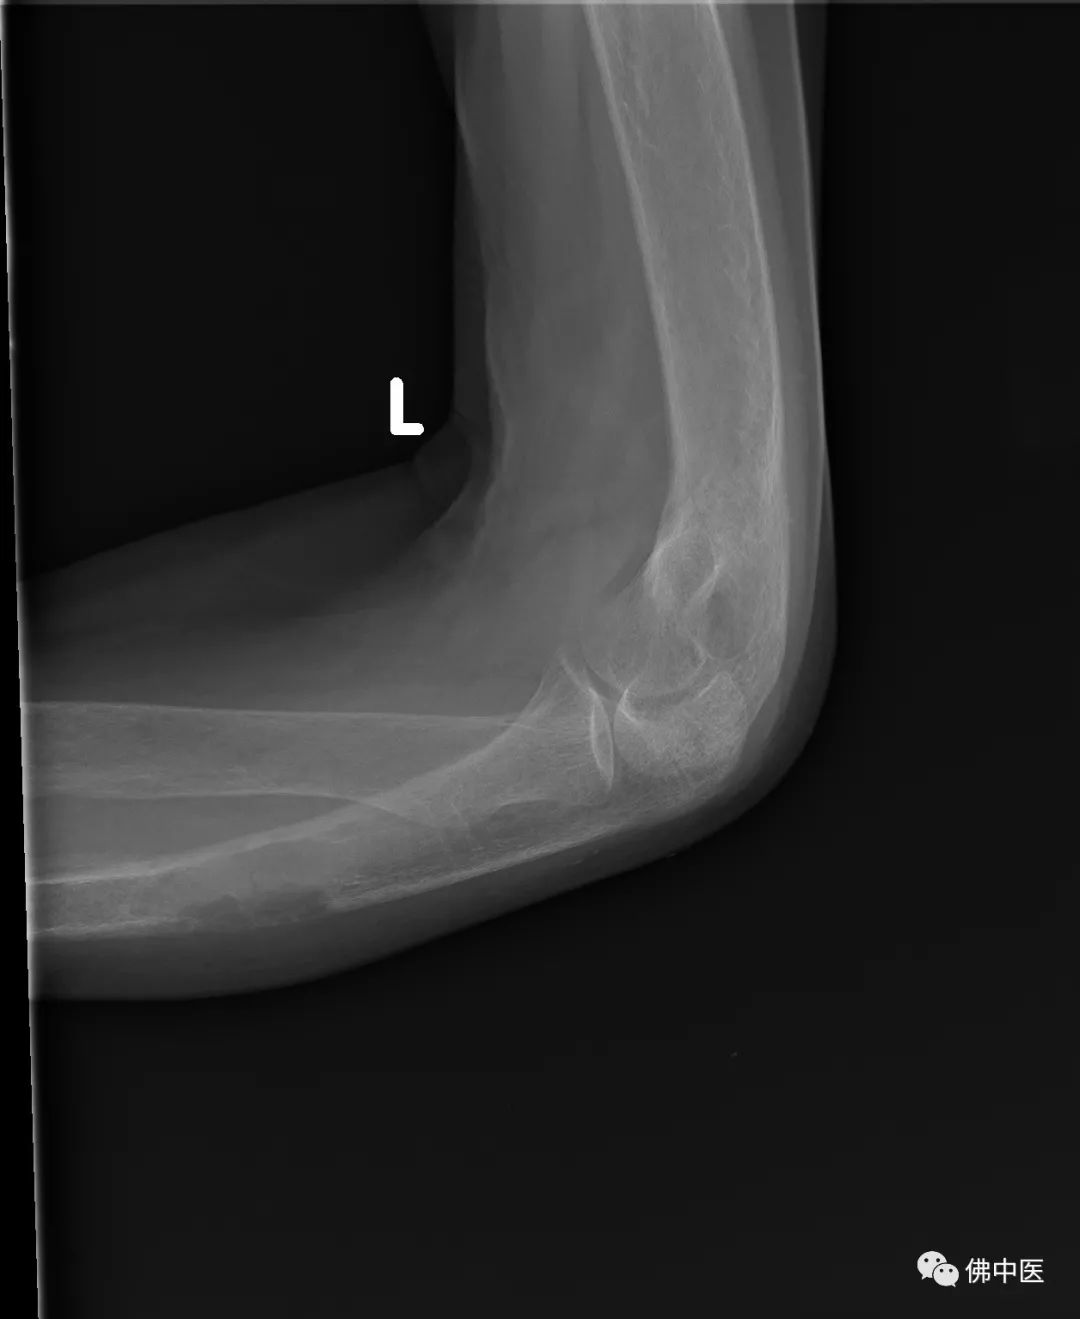

65岁的陈女士,2个多月前无明显诱因下出现左前臂部疼痛,活动不利,自行涂擦药物后症状无明显缓解。10多天前,陈女士的左前臂疼痛症状加重,左手、左上臂部、左肩都感觉疼痛,活动不利,到当地医院进行针灸推拿等对症处理后,症状仍无明显缓解,于是在今年5月到我院骨病专科寻求系统治疗。

x光